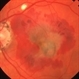

- subfoveal CNVM

- subfoveal choroidal neovascularization

- Fundus photograph of left eye of 65-year-old lady with large subfoveal CNVM